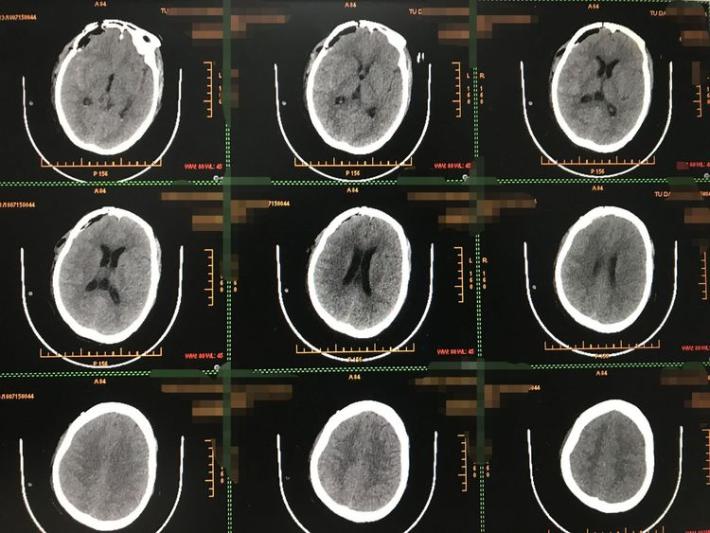

发病当日外院CT示蛛网膜下腔出血

术后CT示术野干净,无出血或梗塞。